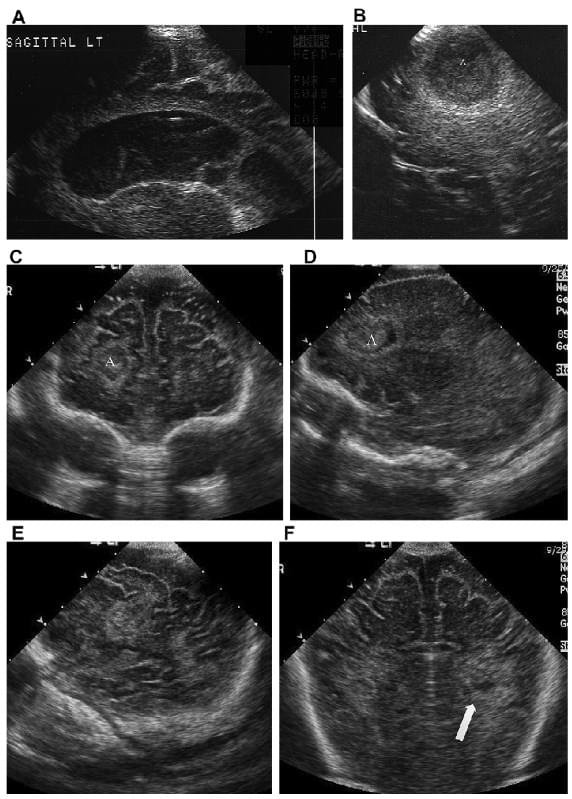

Отже, як його розпізнати? Лікарі можуть використовувати нейросонографію — ультразвукове дослідження мозку малюка. Звучить складно, але це всього лише детальна “фотка” внутрішніх процесів. Окрім того, набряк може проявлятися через зміни у поведінці дитини: напрочуд тихий чи, навпаки, занадто збуджений малюк.